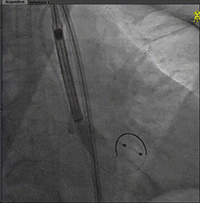

微调alignment及过弓

初始定位

开始释放及评估

缓慢释放